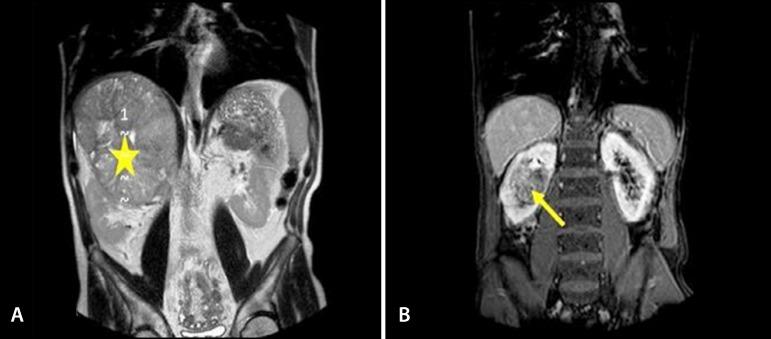

Adrenocortical and renal cell carcinomas rarely invade the right atrium (RA). These neoplasms need surgical treatment, are very aggressive and have poor prognostic and surgical outcomes.

We present a retrospective cohort of nine cases of RA invasion through the inferior vena cava (four adrenocortical carcinomas and five renal cell carcinomas). Over 13 years (2002-2014), nine patients were operated in collaboration with the team of urologists. Surgery was possible in all patients with different degrees of technical difficulty. All patients were operated considering the imaging examinations with the aid of CPB. In all reported cases (renal or suprarenal), the decision to use CPB with deep hypothermic circulatory arrest (DHCA) on surgical strategy was decided by the team of urological and cardiac surgeons.

肾上腺皮质癌和肾细胞癌很少侵犯右心房(RA)。这些肿瘤需要手术治疗,极具侵袭性,预后和手术结果较差。

我们回顾性研究了9例经下腔静脉侵犯右心房的病例(4例肾上腺皮质癌和5例肾细胞癌)。在13年(2002 - 2014年)期间,9例患者与泌尿外科团队合作进行了手术。所有患者均进行了手术,手术难度各异。所有患者均借助体外循环(CPB)并参考影像学检查进行手术。在所有报道的病例(肾或肾上腺)中,关于在手术策略中使用深低温停循环(DHCA)的CPB的决定由泌尿外科和心脏外科团队做出。